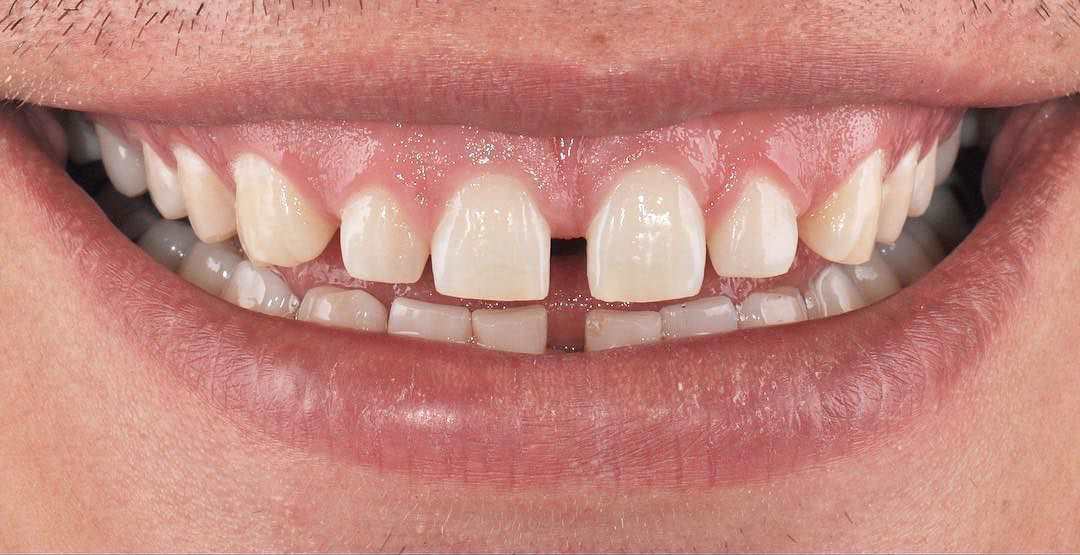

Gülüş Tasarımı

Ağız bakımı denilince akla diş ağrısı, ağız kokusu ve diş kayıpları gibi problemlerin çözümü gelse de günümüzde diş ve diş...

Estetik Diş...

Dişlerimizde renk değişikliği, şekil bozukluğu veya madde kaybı olduğunda hem dişlerimiz güzel olsun ama zarar görmesin isteriz.